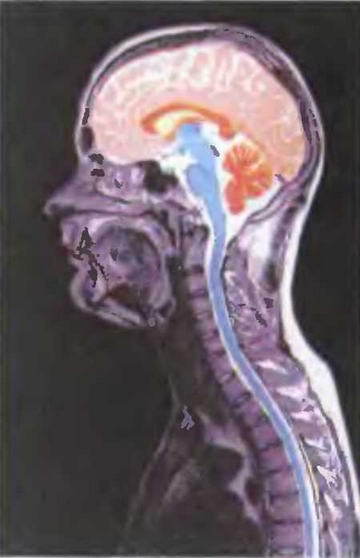

За угасание памяти ответственны участки коры лобной доли с двух сторон. В этих "центрах" отмечается увеличение активности, а вот в правом гиппокампе — извилине морского конька — на основании височной доли активность угасает. Оно и неудивительно, если учесть современные воззрения, согласно которым именно гиппокамп является хранилищем нашей памяти.